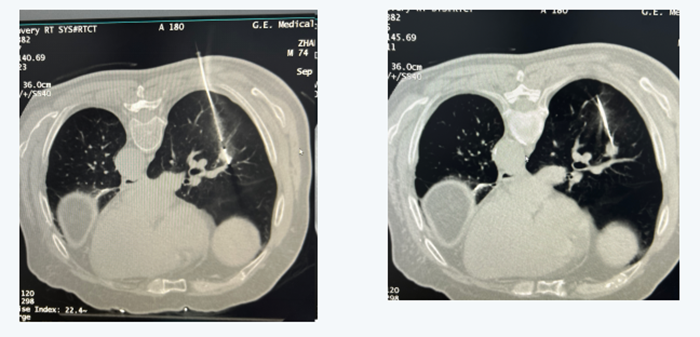

3年前张先生在外院诊断为左侧肺癌并行手术切除治疗,今年6月复查后发现右肺下叶又出现一个约1*0.8cm的肺结节,考虑复发可能性大。由于该肿块体积较小,位置比较深,且周围血管丰富,穿刺活检难度较大,建议张先生手术探查。因张先生术后肺功能较差,且合并多种基础病,拒绝进一步手术。

经了解,曾麟团队有丰富的经皮穿刺活检经验,至今已成功进行上千例各种高难度穿刺活检,故张先生慕名来我院就诊,经过仔细阅片及团队多次讨论后,曾麟在CT引导下行经皮穿刺,在毫厘之间避开数根肺内血管,一针到位,成功取到病理组织,最终病理结果证实是肺腺癌。根据患者病情为其采用经皮微波消融术,该手术创伤小,时间短,手术前后不到20分钟,张先生当晚即可下地行走,术后5天出院。在术后一个月复查时,PET-CT显示整个术区肿瘤活性完全消除,达到局部根治的效果,张先生和他的家属非常满意。